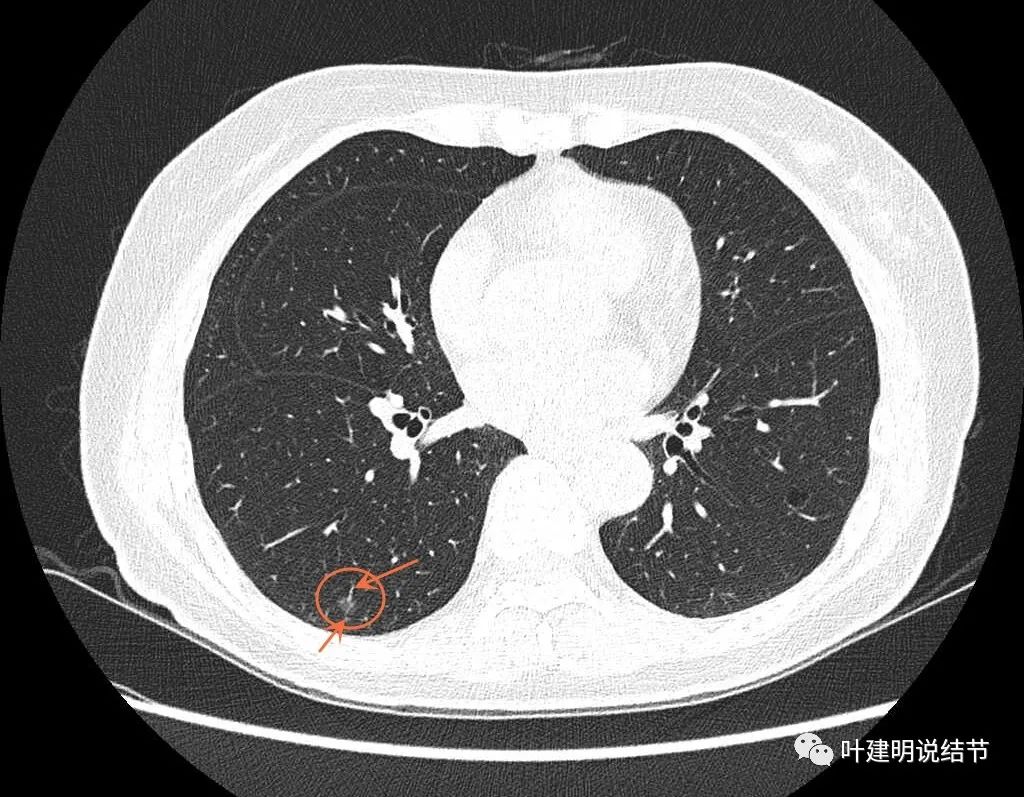

病灶8:右下叶磨玻璃结节了,轮廓清,血管贴边,边缘显毛糙。

有明显小血管进入,小血管有异常增粗。从密度考虑不典型增生可能性大,但因血管进入升一级考虑,原位癌可能性大点。如果没有上叶病灶6存在,此灶可随访,近期风险不算高。

病灶8重建后显示血管与结节间没有间隙,而且瘤肺边界很清。